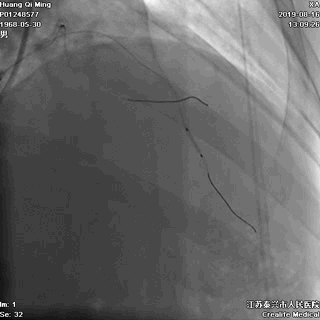

LAD PCI过程

手术器械:

7F EBU3.5

0.014“ Runthrough NS

2.0*20 Maverick

2.5*10 切割球囊

2.5*12 Quantum Maverick球囊

2.0*25 药物洗脱球囊

2.5*25 药物洗脱球囊

导丝通过病变抵达血管远段

8atm,2.0*20球囊行PTCA

8atm,2.0*10 切割球囊对斑块进行切割

16atm,NC球囊对斑块进行预处理